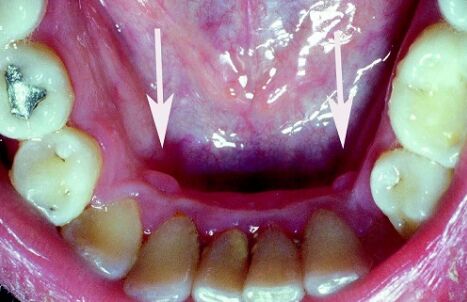

15.病灶如附圖箭頭所示。關於此情況的敘述,下列何者錯誤?(A)診斷為 retrocuspid papilla (B)好發於兒童及年輕人 (C)病因為慢性刺激 (D)不需手術切除